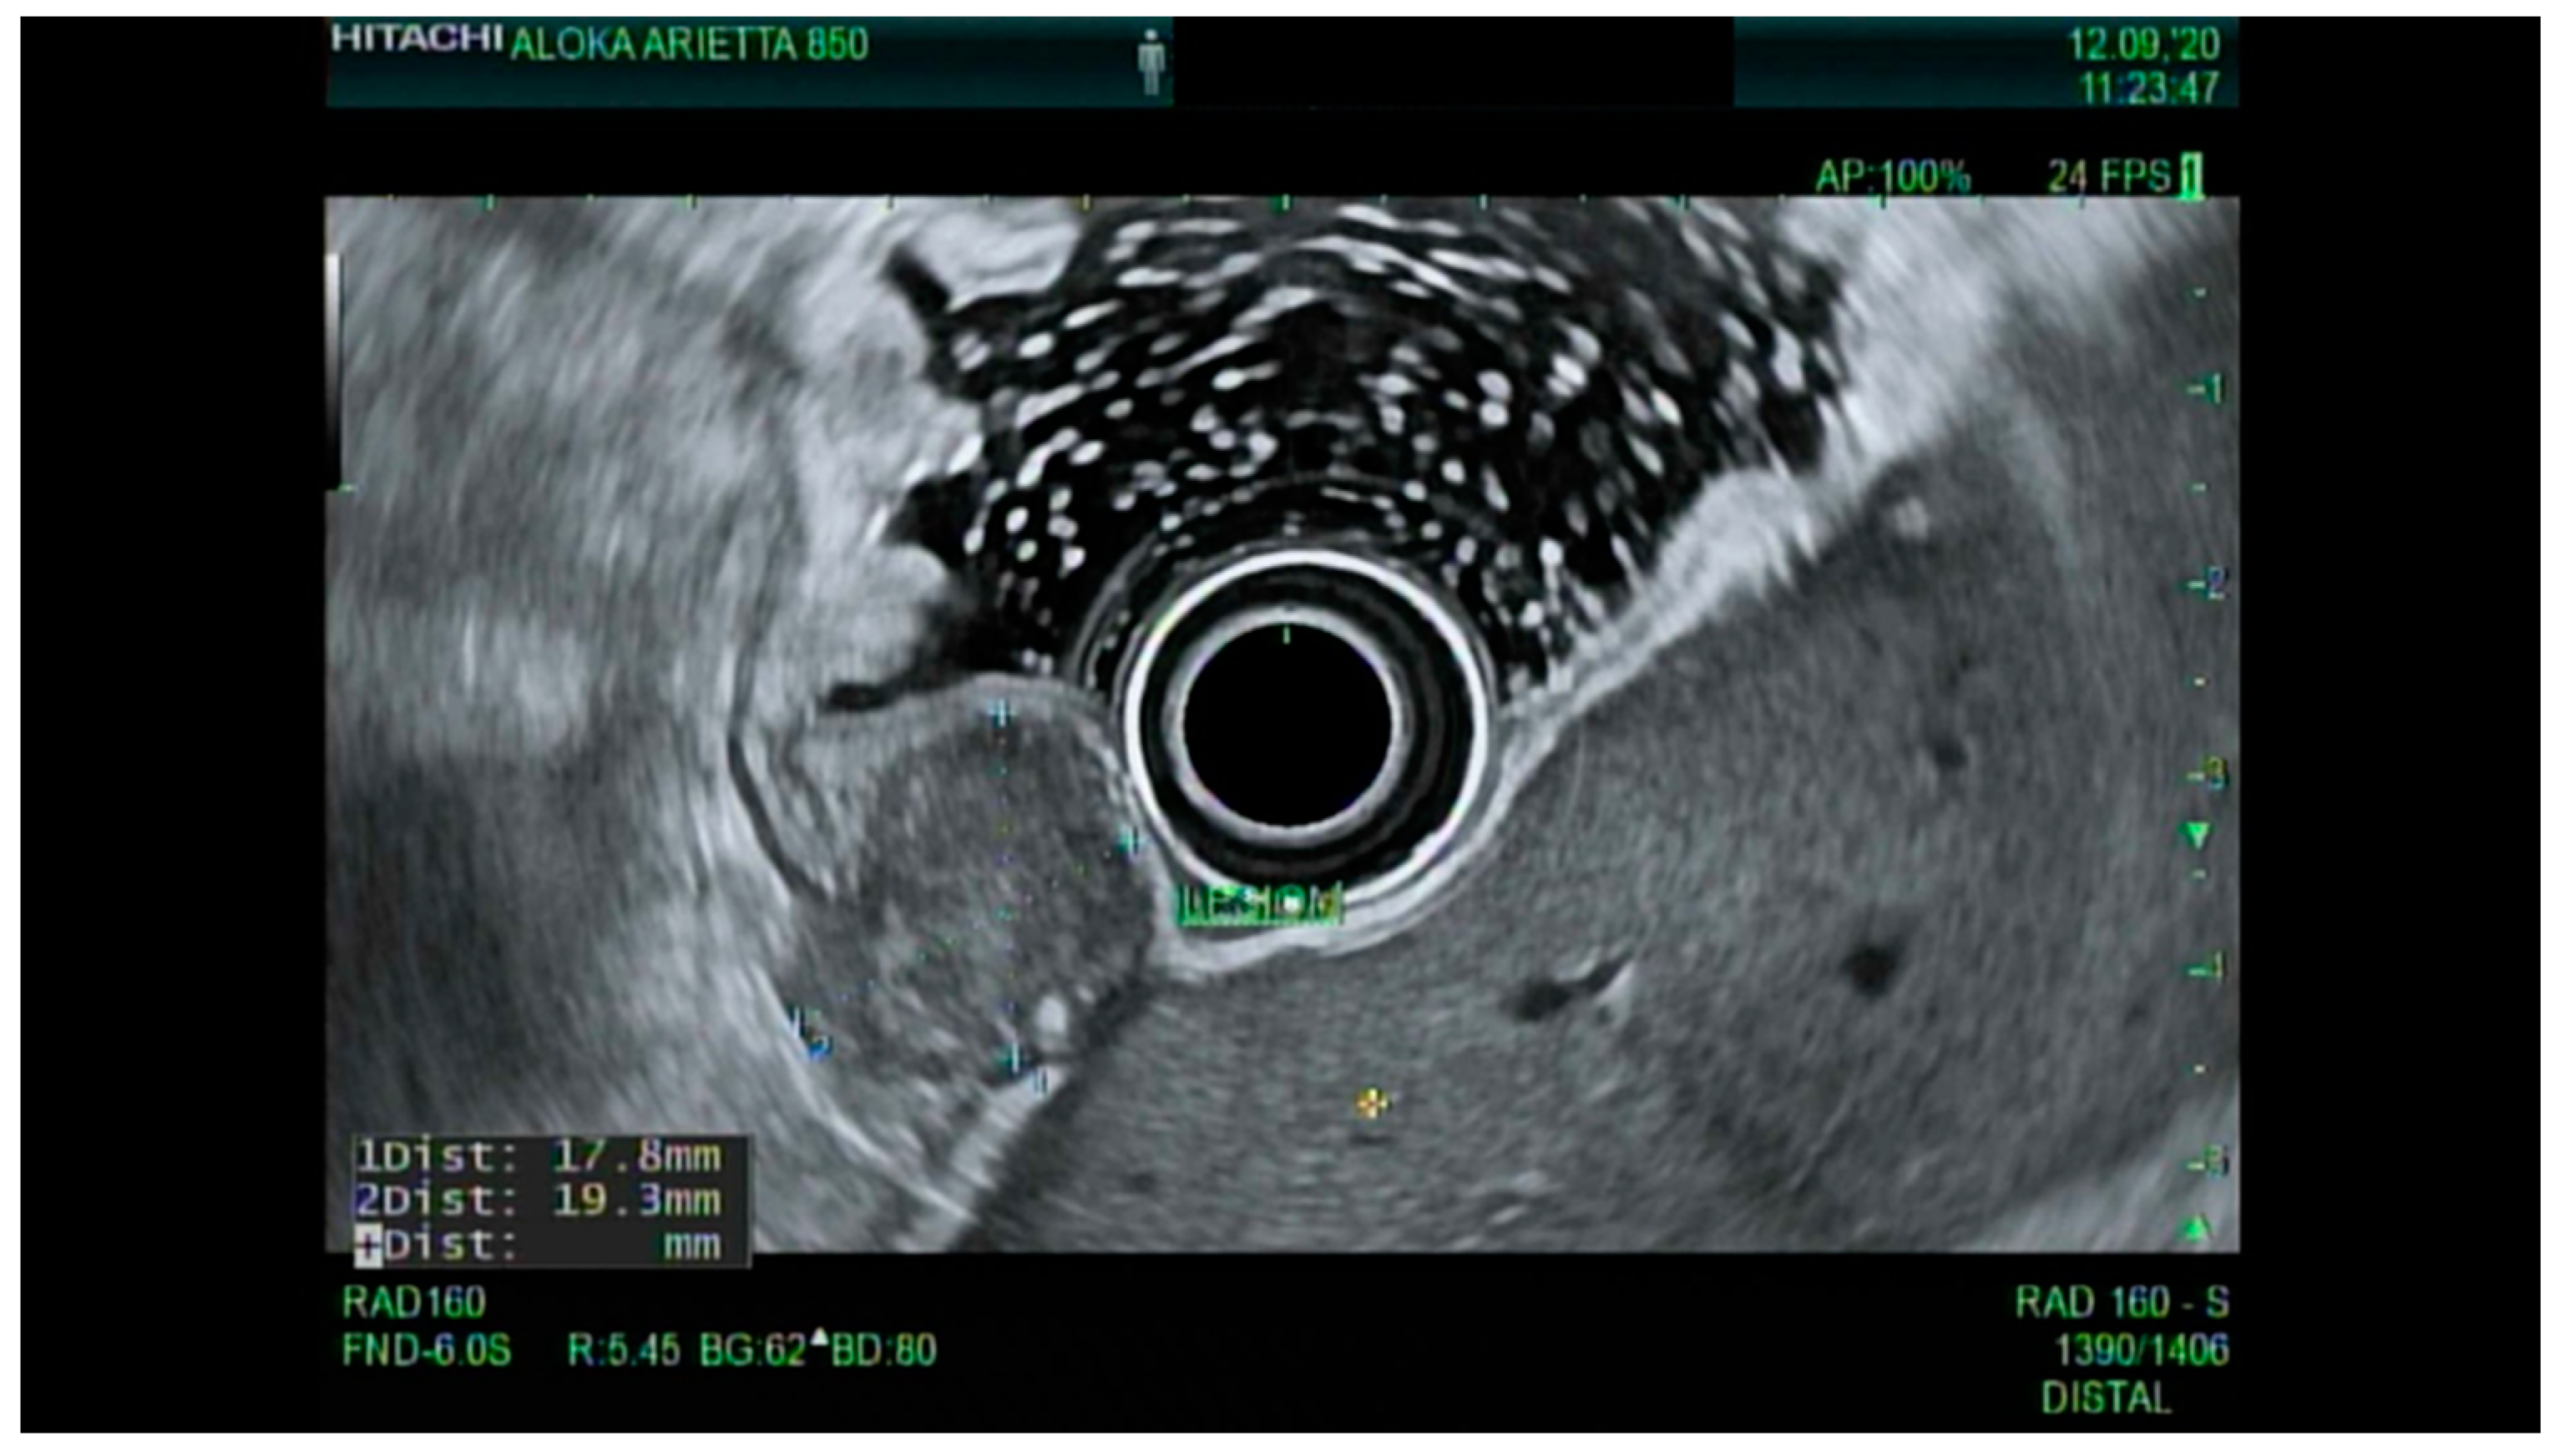

4.3. Endoscopic Ultrasound in Staging of Gastric Cancer

- Spolverato, G.; Ejaz, A.; Kim, Y.; Squires, M.H.; Poultsides, G.A.; Fields, R.C.; Schmidt, C.; Weber, S.M.; Votanopoulos, K.; Maithel, S.K.; et al. Use of Endoscopic Ultrasound in the Preoperative Staging of Gastric Cancer: A Multi-Institutional Study of the US Gastric Cancer Collaborative. J. Am. Coll. Surg. 2015, 220, 48–56. [Google Scholar] [CrossRef] [PubMed]

- Mocellin, S.; Pasquali, S. Diagnostic accuracy of endoscopic ultrasonography (EUS) for the preoperative locoregional staging of primary gastric cancer. Cochrane Database Syst. Rev. 2015, 2015, CD009944. [Google Scholar] [CrossRef]

- Redondo-Cerezo, E.; Martínez-Cara, J.G.; Jiménez-Rosales, R.; Valverde-López, F.; Caballero-Mateos, A.; Jérvez-Puente, P.; Ariza-Fernández, J.L.; Úbeda-Muñoz, M.; López-De-Hierro, M.; De Teresa, J. Endoscopic ultrasound in gastric cancer staging before and after neoadjuvant chemotherapy. A comparison with PET-CT in a clinical series. United Eur. Gastroenterol. J. 2017, 5, 641–647. [Google Scholar] [CrossRef]